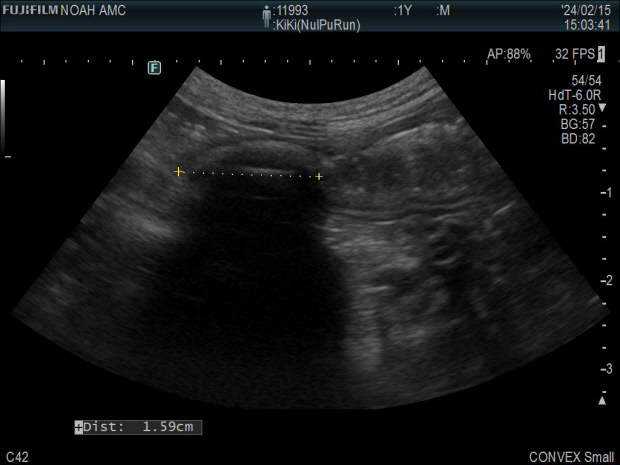

![]() 과일씨를 먹고 장폐색 증상이 온 고양이 키키의 복부 초음파 사진. <이영아씨 제공> |

엑스레이와 초음파 촬영 결과가 전날과 크게 차이가 나자 수의사는 장폐색이 왔음을 직감하고 응급수술이 가능한 동물병원으로 급하게 전원시켜 수술을 받을 수 있도록 했다.

이씨는 “수술을 하지 않으면 키키가 죽을 수도 있는 응급이어서 병원비 등을 고민할 상황이 아니었다”며 “수술 후 장 속에서 1.2~1.5㎝의 동그란 이물질이 나왔는데 알고 보니 감 씨였다”고 전했다.